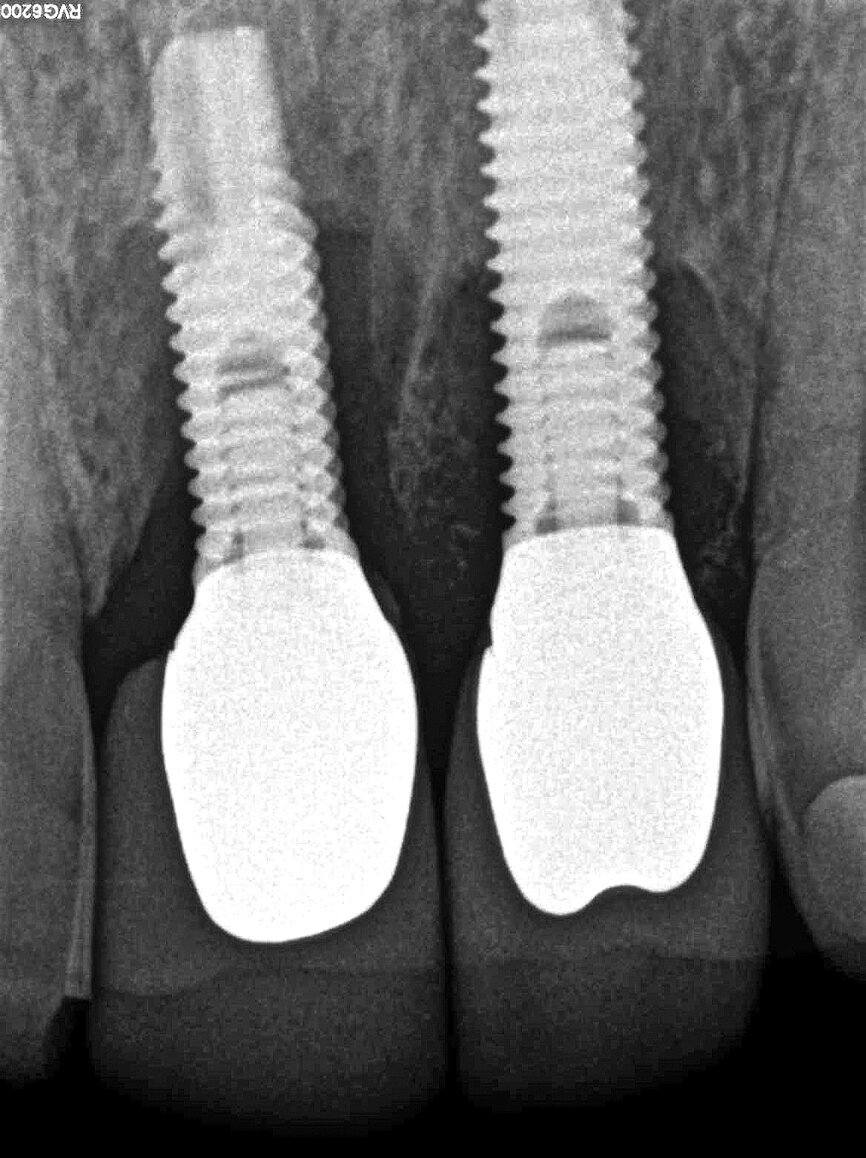

A 59-year-old patient presented to the practice complaining about minor exudate at his dental implants in the anterior region (Fig. 1). Probing revealed a deep circular pocket around the implants during the initial examination. Mobility of the implants was, however, not detected. As suspected, the radiographic examination confirmed an advanced peri-implantitis at the recently placed implants (Fig. 2).

Finally, the surgical area was covered with the bioresorbable membrane, and the flap was re-adapted with interrupted sutures in order to achieve a complete and impermeable wound closure (Fig. 8). The radiograph taken immediately after surgery showed the filled defect (Fig. 9). Good osseous consolidation at the enamel-cement junction of the adjacent teeth could be seen on the follow-up radiograph taken 24 months later (Fig. 10).